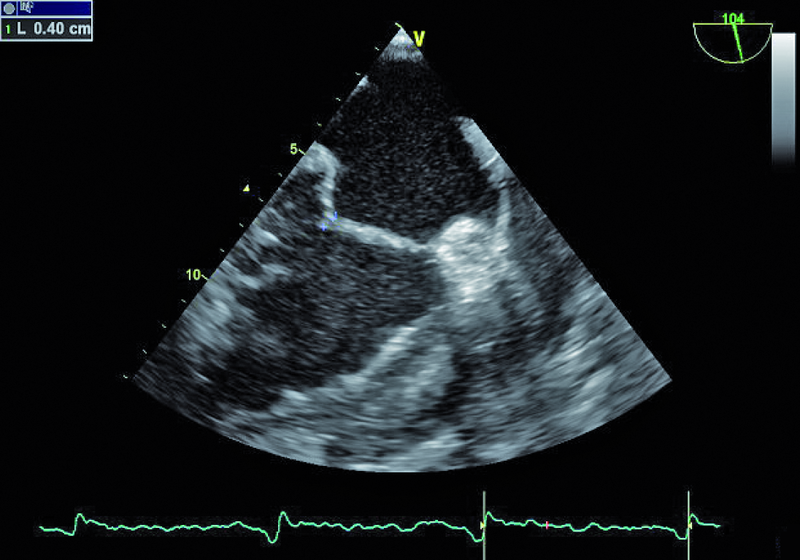

Niedomykalność zastawki mitralnej o etiologii niedokrwiennej pogarsza rokowanie u chorego z chorobą wieńcową i istotnie obniża komfort życia. Fala zwrotna w prezentowanym materiale sięga ujścia żył płucnych (ryc. 1), a ciśnienie w jamie prawej komory jest podwyższone (ryc. 2). U chorych, u których nie ma wskazań do rewaskularyzacji lub u chorych z chorobami współistniejącymi poszukuje się innych metod interwencji poza chirurgiczną naprawą. Punktem wyjścia dla rozważań o możliwości leczenia niechirurgicznego jest dokładna ocena anatomii zastawki. Wykorzystuje się dane zarówno z badania przezklatkowego, jak i przezprzełykowego, choć oczywiście optymalnym rozwiązaniem byłoby zastosowanie obrazowania trójwymiarowego. Sporo uwagi poświęca się ostatnio naprawie płatków zastawki za pomocą tzw. urządzenia mitraclip. Techniką tą można interesować się zwłaszcza w kontekście chorych bez istotnego poszerzenia pierścienia zastawki (w prezentowanym przypadku średnica pierścienia nie przekraczała 35 mm), a z dostatecznie dużą ilością tkanki tworzącej jej płatki. Założeniem techniki mitraclip, przypominającej zabieg chirurgiczny Alfieriego, jest połączenie segmentów środkowych płatka przedniego i tylnego. Skutecznie wykonany zabieg poprawia koaptację płatków i zapoczątkowuje odwrotny remodeling lewej komory, zmniejszający z kolei udział tzw. sił pociągających. Na co trzeba zwrócić uwagę, oceniając pacjenta z niedomykalnością mitralną, towarzyszącą chorobie niedokrwiennej? Niedomykalność (wg podziału Carpentiera typ 3b) powinna rzeczywiście powstawać między segmentami A2 a P2 (ryc. 3), ponieważ tylko w takim wypadku połączenie płatków i wytworzenie dwóch osobnych ujść może choremu przynieść korzyść. Ważnym elementem oceny jest uzyskanie projekcji przezżołądkowej poprzecznej. Ta projekcja bardzo dobrze ilustruje wielkość płatków i ich wzajemną relację (ryc. 4 – większy płatek tylny znajduje się bliżej głowicy). Przeciwwskazaniami do zabiegu implantacji mitraclip może być nadmierna grubość płatków, utrudniająca ich uchwycenie przez ramiona urządzenia, mniejsza niż 2 mm długość koaptacji oraz większa niż 11 mm głębokość koaptacji w stosunku do linii podstawnej pierścienia zastawki. Wymienionych cech nie potwierdzono w badaniu (ryc. 5, 6) i zakwalifikowano chorego do zabiegu w trybie planowym. Warto pamiętać, że echokardiografia służy nie tylko ocenie wskazań do zabiegu, ale stanowi także podstawę jego monitorowania.